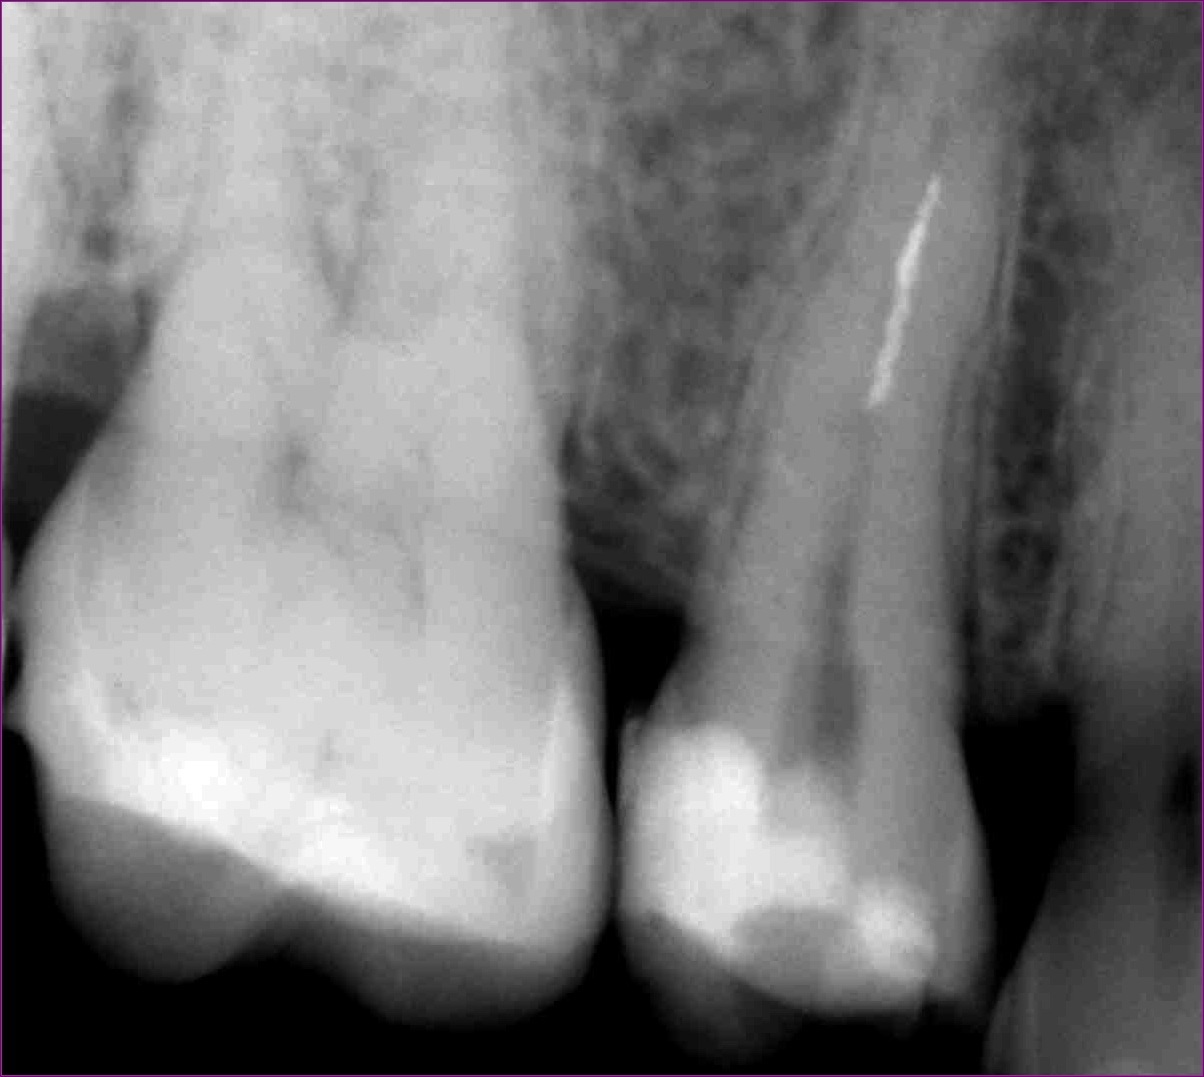

A hölgy örömmel hallotta, hogy hála a mikroszkópos endodonciának, jó eséllyel orvosolható a problémája: így a bajba került fogat meg lehet menteni a kihúzástól. Az érintett jobb felső ötös fogról a páciens már egy kis fogfelvétellel érkezett (lásd fentebb).

A gyökérkezelés menetében az első lépés a diagnózis, amely többek között az érintett fog(ak)ról készített röntgenfelvételen alapul. A röntgen megtekintésekor szakértőnknek feltűnt, hogy valószínűleg nem egy, hanem két betört fragmentumról van szó. Ezek a fogak gyakran két csatornával rendelkeznek, illetve ebben az esetben egy érdekes variációval: a két csatornának közös vége van. Ilyenkor az egymás felé ívelő gyökércsatornák meglehetősen görbék lehetnek – tipikus helyei a tűtöréseknek.

A röntgenfelvétel igazolta a gyanút

Először a szájpadlás felőli gyökércsatornában tártuk fel a tűt. Óvatosan, a megfelelő technikát alkalmazva sikerült eltávolítani a nagyjából 4 mm-es darabot. Ilyenkor készítünk egy kontrollröntgent, hogy lássuk, valóban nem maradt bent semmi az eltávolított tűből. Ekkor vált biztossá dr. Kovács Kitti gyanúja: van még egy műszer a fogban.